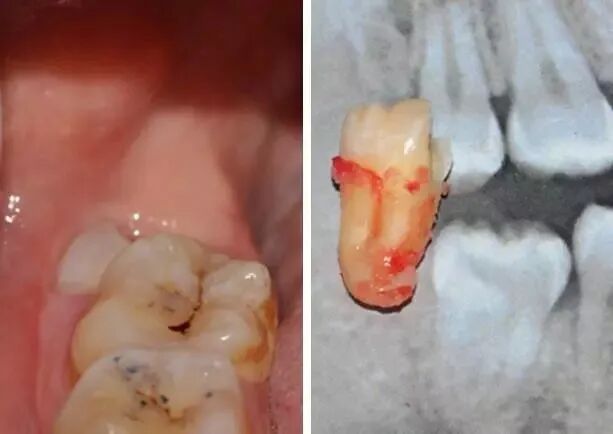

图3:牙根曲度大,但是短小,故而可以认为根部骨阻力小。那就很简单喽。